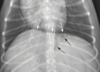

DV or VD?

VD

DV or VD ?

DV

When is a single domed diaphragm seen on a VD?

when XR beam is centred over mid-abdo

When is a single domed diaphragm seen on a DV?

when XR beam is centred over mid-thorax